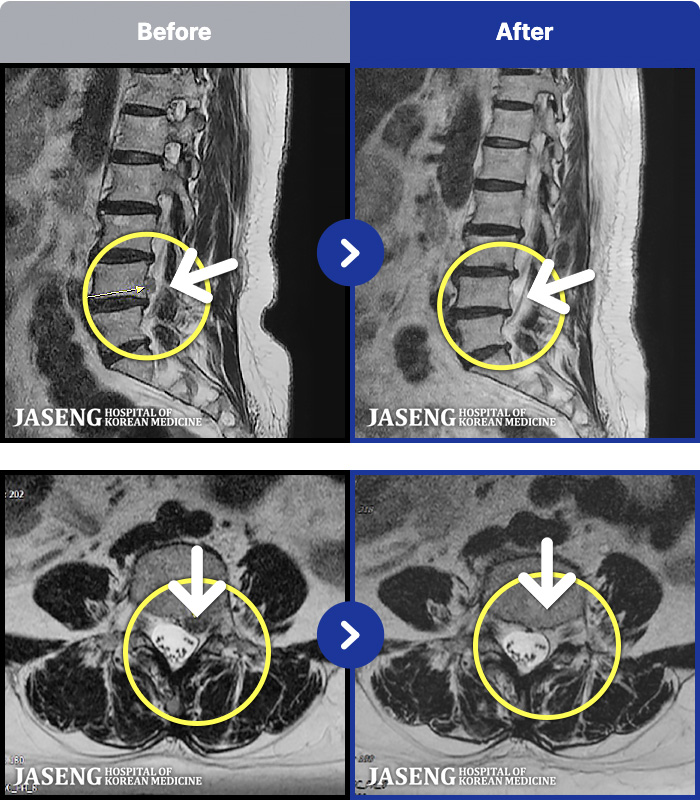

MRI ġ

1,237 MRI ũ ʸ Ȯϼ.